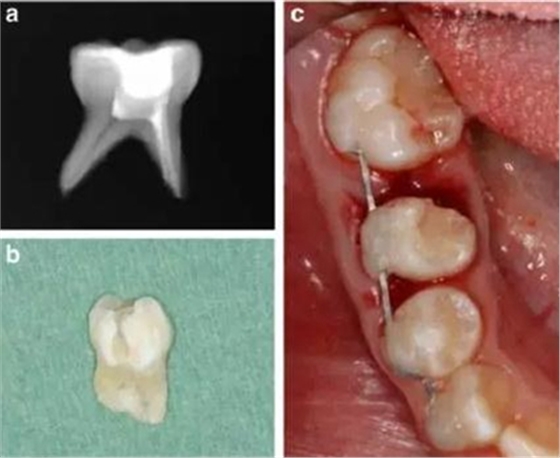

牙槽固連技術(shù)包括在局麻下拔除乳磨牙,然后進(jìn)行近中根的體外根管治療,對(duì)牙冠做復(fù)合樹(shù)脂的修復(fù),進(jìn)行2mm的根尖切除術(shù)和偏側(cè)牙根切除。為了達(dá)成牙槽固連,我們采用了根尖孔閉合且在口外干燥60分鐘以上脫位牙的處理方法。用刮治器從根面上收集牙周膜細(xì)胞。拔除6分鐘后,用鹽溶液沖洗牙槽窩,將近中牙根帶輕微壓力重新植入。為了保持牙齒穩(wěn)定,從右側(cè)尖牙到右側(cè)第一磨牙應(yīng)用0.016’’*0.022’’不銹鋼方絲作為牙弓夾板。